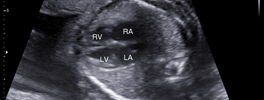

2D Sonography-Foetal Heart